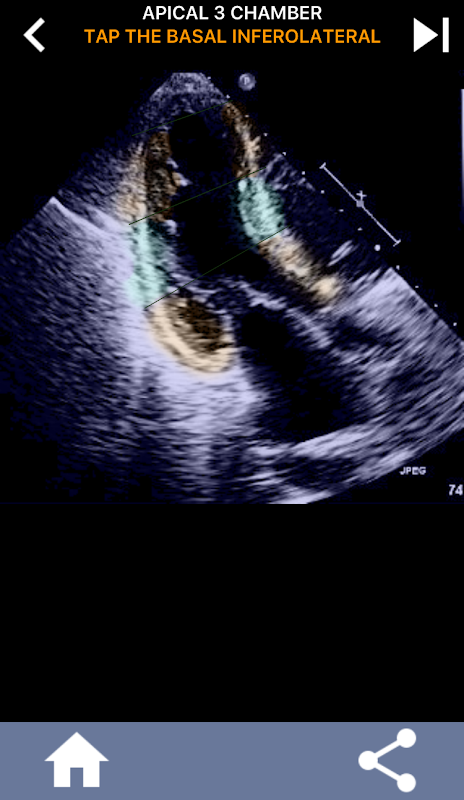

초음파 심장 초음파 검사는 좌심실의 미국 심장 협회 심장 세분화를 자기 공명 영상, 심장 핵 검사 등과 같은 다른 많은 영상 진단법에서 널리 사용되는 표준 인 17 개 세그먼트로 학습하는 것이 필수적입니다. 영향을받는 세그먼트 및 기능의. 여러 번 에코를 읽는 사람이 "무엇을 보았습니까?"라고 묻습니다. 영향을받은 지역의 정확한 위치로 회신하는 것이 예상됩니다.

이 응용 프로그램은 AHA로 구분 된 심근을 보여주는 모든 반향보기를 포함하고 올바른 부분을 탭하도록 퀴즈 것입니다. 나는 개인적으로 빨리 반복적 인 퀴즈가 나를 위해 가장 잘 작동한다는 것을 알았다. 나는 주제를 빨리 배우고 암기해야한다. 당신이 에코 / TTE를 공부하는 초음파 학생이라면, 이것은 당신의 연구에 훌륭한 보완책이 될 것이라고 생각합니다.